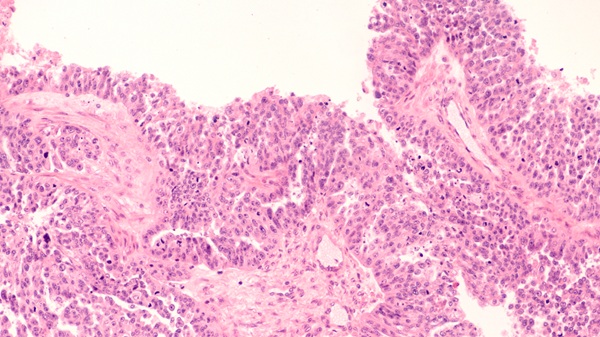

- Double-Contrast MRI Technique Identifies Small Tumors